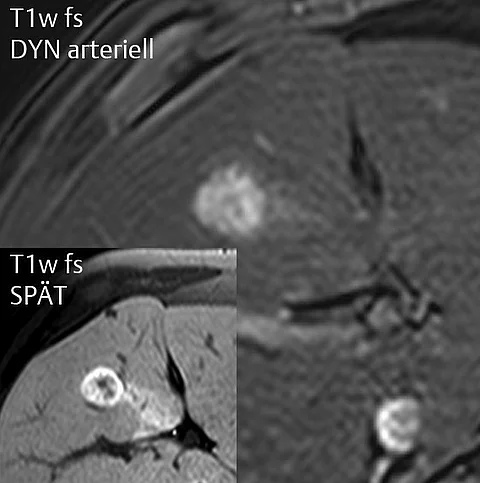

Bei einer Routineuntersuchung stellt sein Betriebsarzt bei dem 25-jährigen Mann einen schmerzlosen Knoten im rechten Schilddrüsenlappen fest. Bildgebung und Labor verraten worum es sich handelt – Wissen Sie die Diagnose?